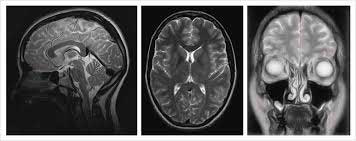

| Диагностика | МРТ, КТ головного мозга. | Серповидноклеточная анемия. |

- при исследовании сосудов головного мозга с использованием контрастных веществ не выявляется никаких нарушений, а при компьютерной и магнитно-резонансной томографии могут быть обнаружены небольшие участки пониженной плотности, но это не всегда возможно, особенно если инфаркт небольшой.

В процессе диагностики важную роль играет МРТ, позволяющая обнаружить патологические образования диаметром от 1,7 мм, а также определить их форму и местоположение. Меньшие новообразования не удается выявить ни одним из доступных методов.

Людям, относящимся к группе риска, рекомендуется ежегодно проходить МРТ, что позволяет отслеживать динамику заболевания и своевременно корректировать терапию.